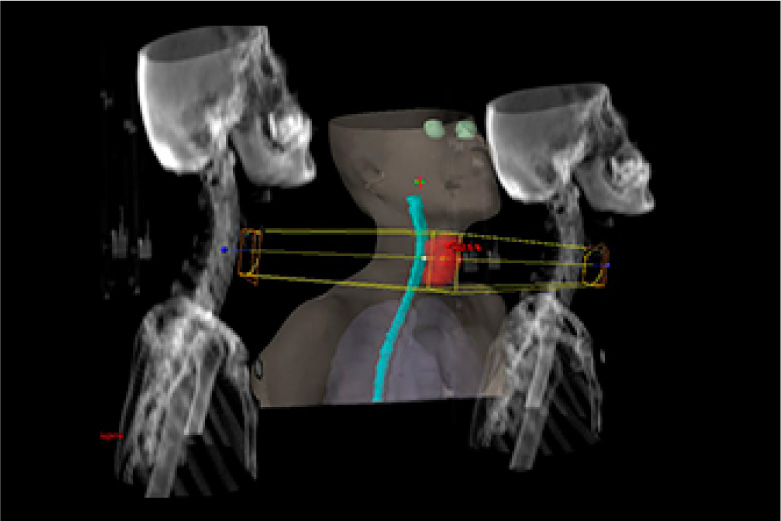

放射線治療とは身体できた病巣部に放射線を照射しがん等の病気を治す治療法です。

手術と比較し身体への負担が少なく病巣部を安全かつ効果的に治療することができます。

当院で使用する放射線は高エネルギーX線及び電子線で直線加速器(リニアック)を用いて人工的に放射線を作るため目的に応じた線質、強さ、量に調整することができます。

実際の治療ではまず治療開始前にCT撮影を行い、照射する場所、範囲、放射線の量等を専用の機器を用いて決定します。(下図参照)これをもとに治療時には装置に搭載されたX線撮影装置、CT装置にて画像を撮影し3次元的に位置照合を行い計画された方向より照射します。

治療装置は360度どの方向からでも照射可能で病巣を多方向から正確に照射することで治療効果の向上、病巣周囲の正常組織の線量を減らすことができます。

治療は1回約10分程度で(初回のみ20~30分)通常1日1回で20~30回程度行います。通常照射中は痛み等特になく身体への負担は少ないですが毎日休まずに行うことが重要となります。(治療は平日のみで土日祝日はお休みです)

バリアン True Beam